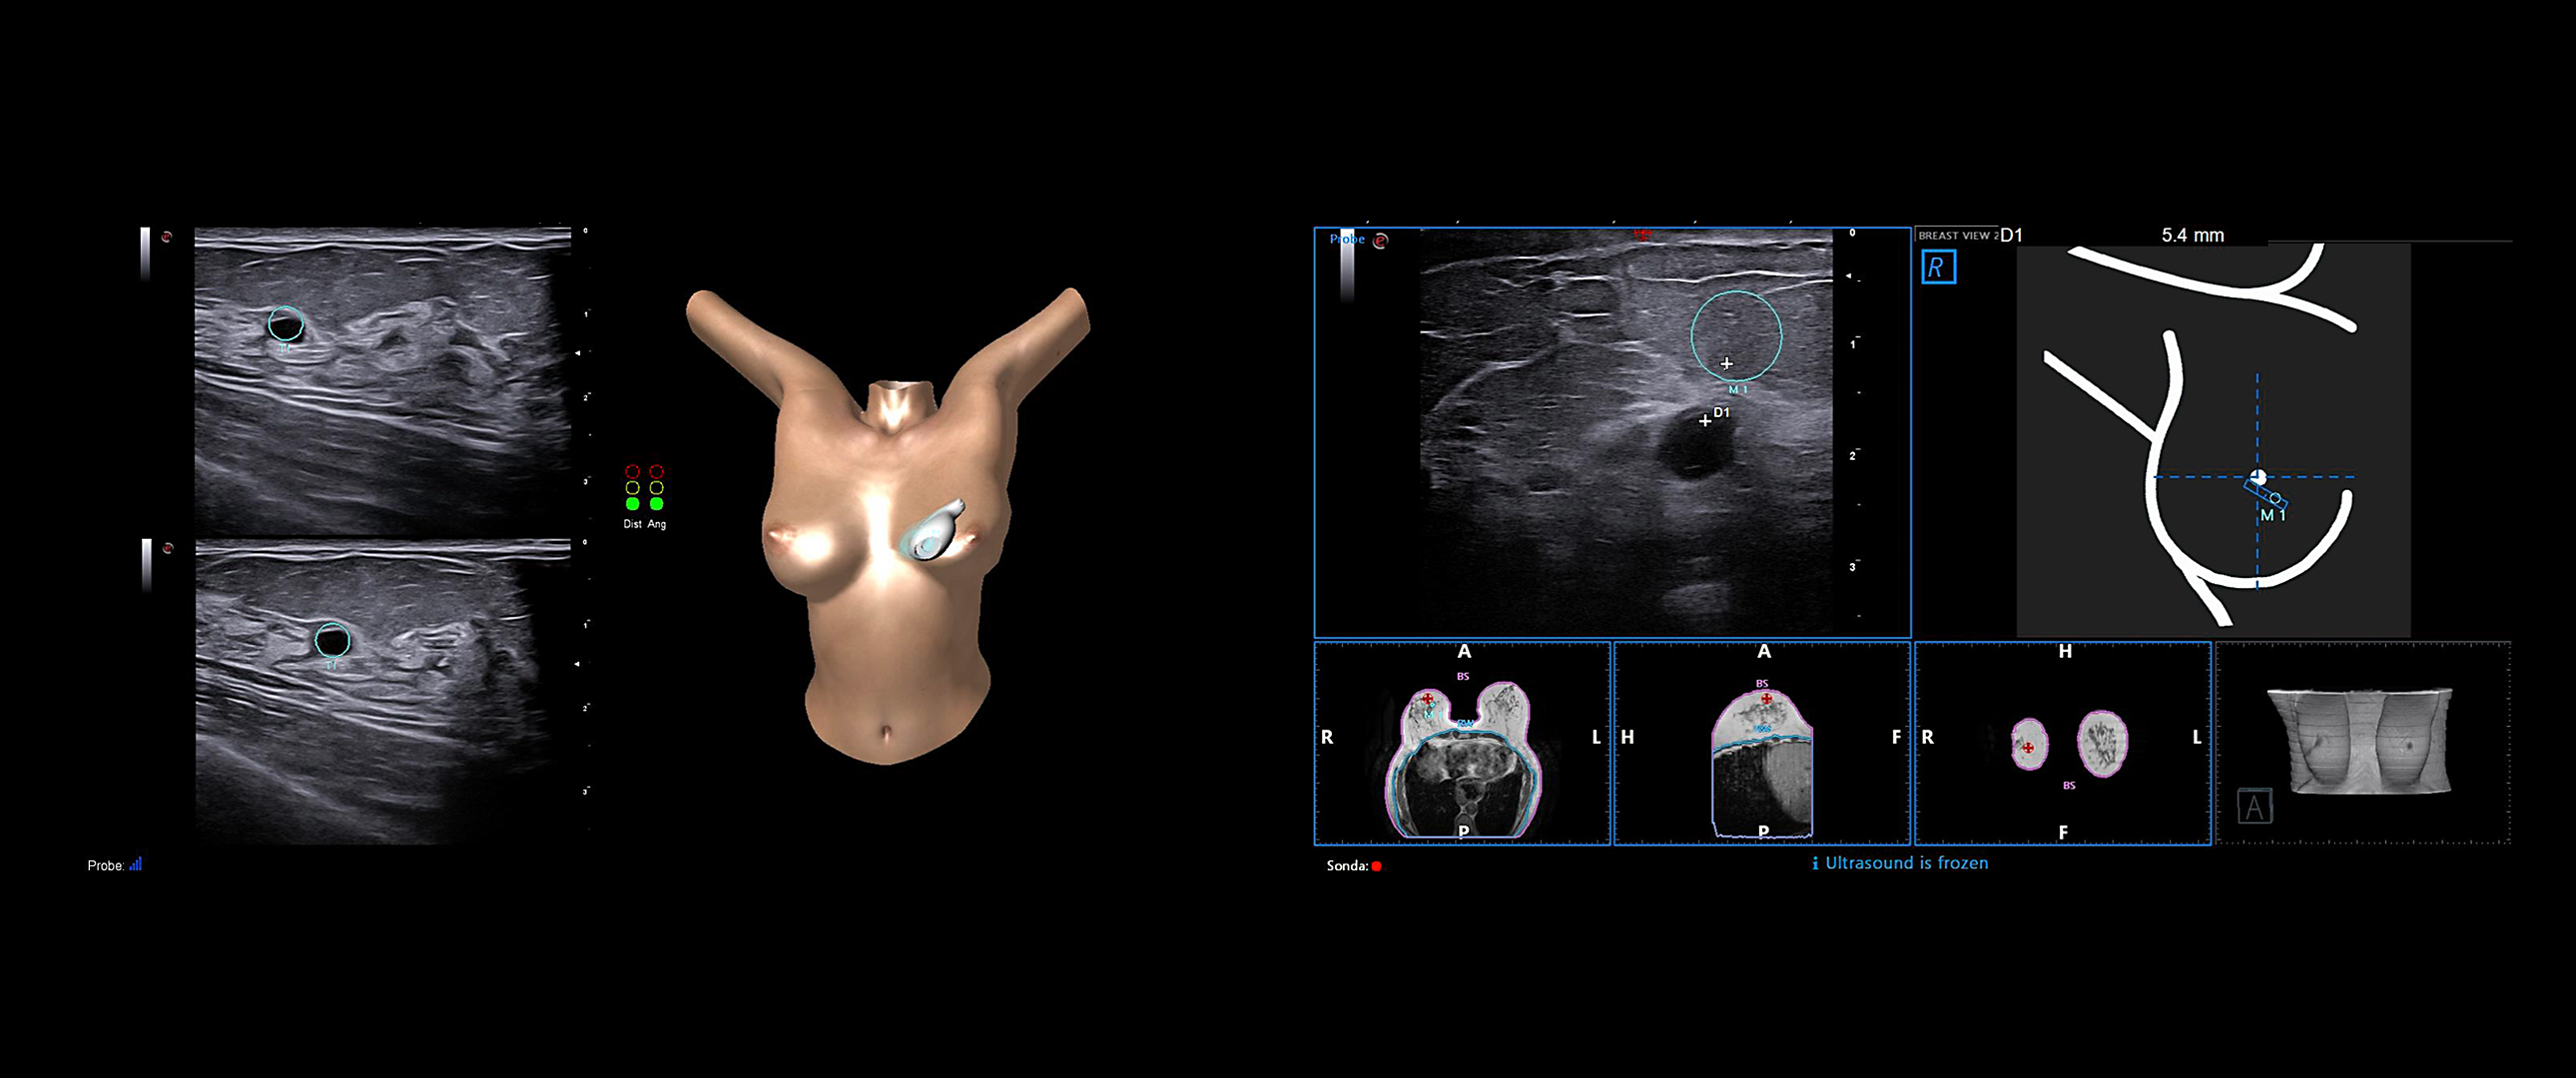

BreastNav™ & BreastNav™ MRI offer the full breast package for a multimodality approach in one of the most mobile and variable organs in the human body, giving real-time feedback on the scanned area for easy follow-up on a specific target.

BreastNav™ is an advanced technology based on adaptive 3D modeling, which enables quick, easy and effective follow-up of breast lesions, clip insertion, injury, or to provide an indication to the surgeon with regard to location.

BreastNav™ MRI is a unique feature in the market, which can perform real-time fusion imaging on the breast between the prone MRI and supine US datasets, based on 3D-model adaptive A.I. technology, aimed at supporting second-look examinations.